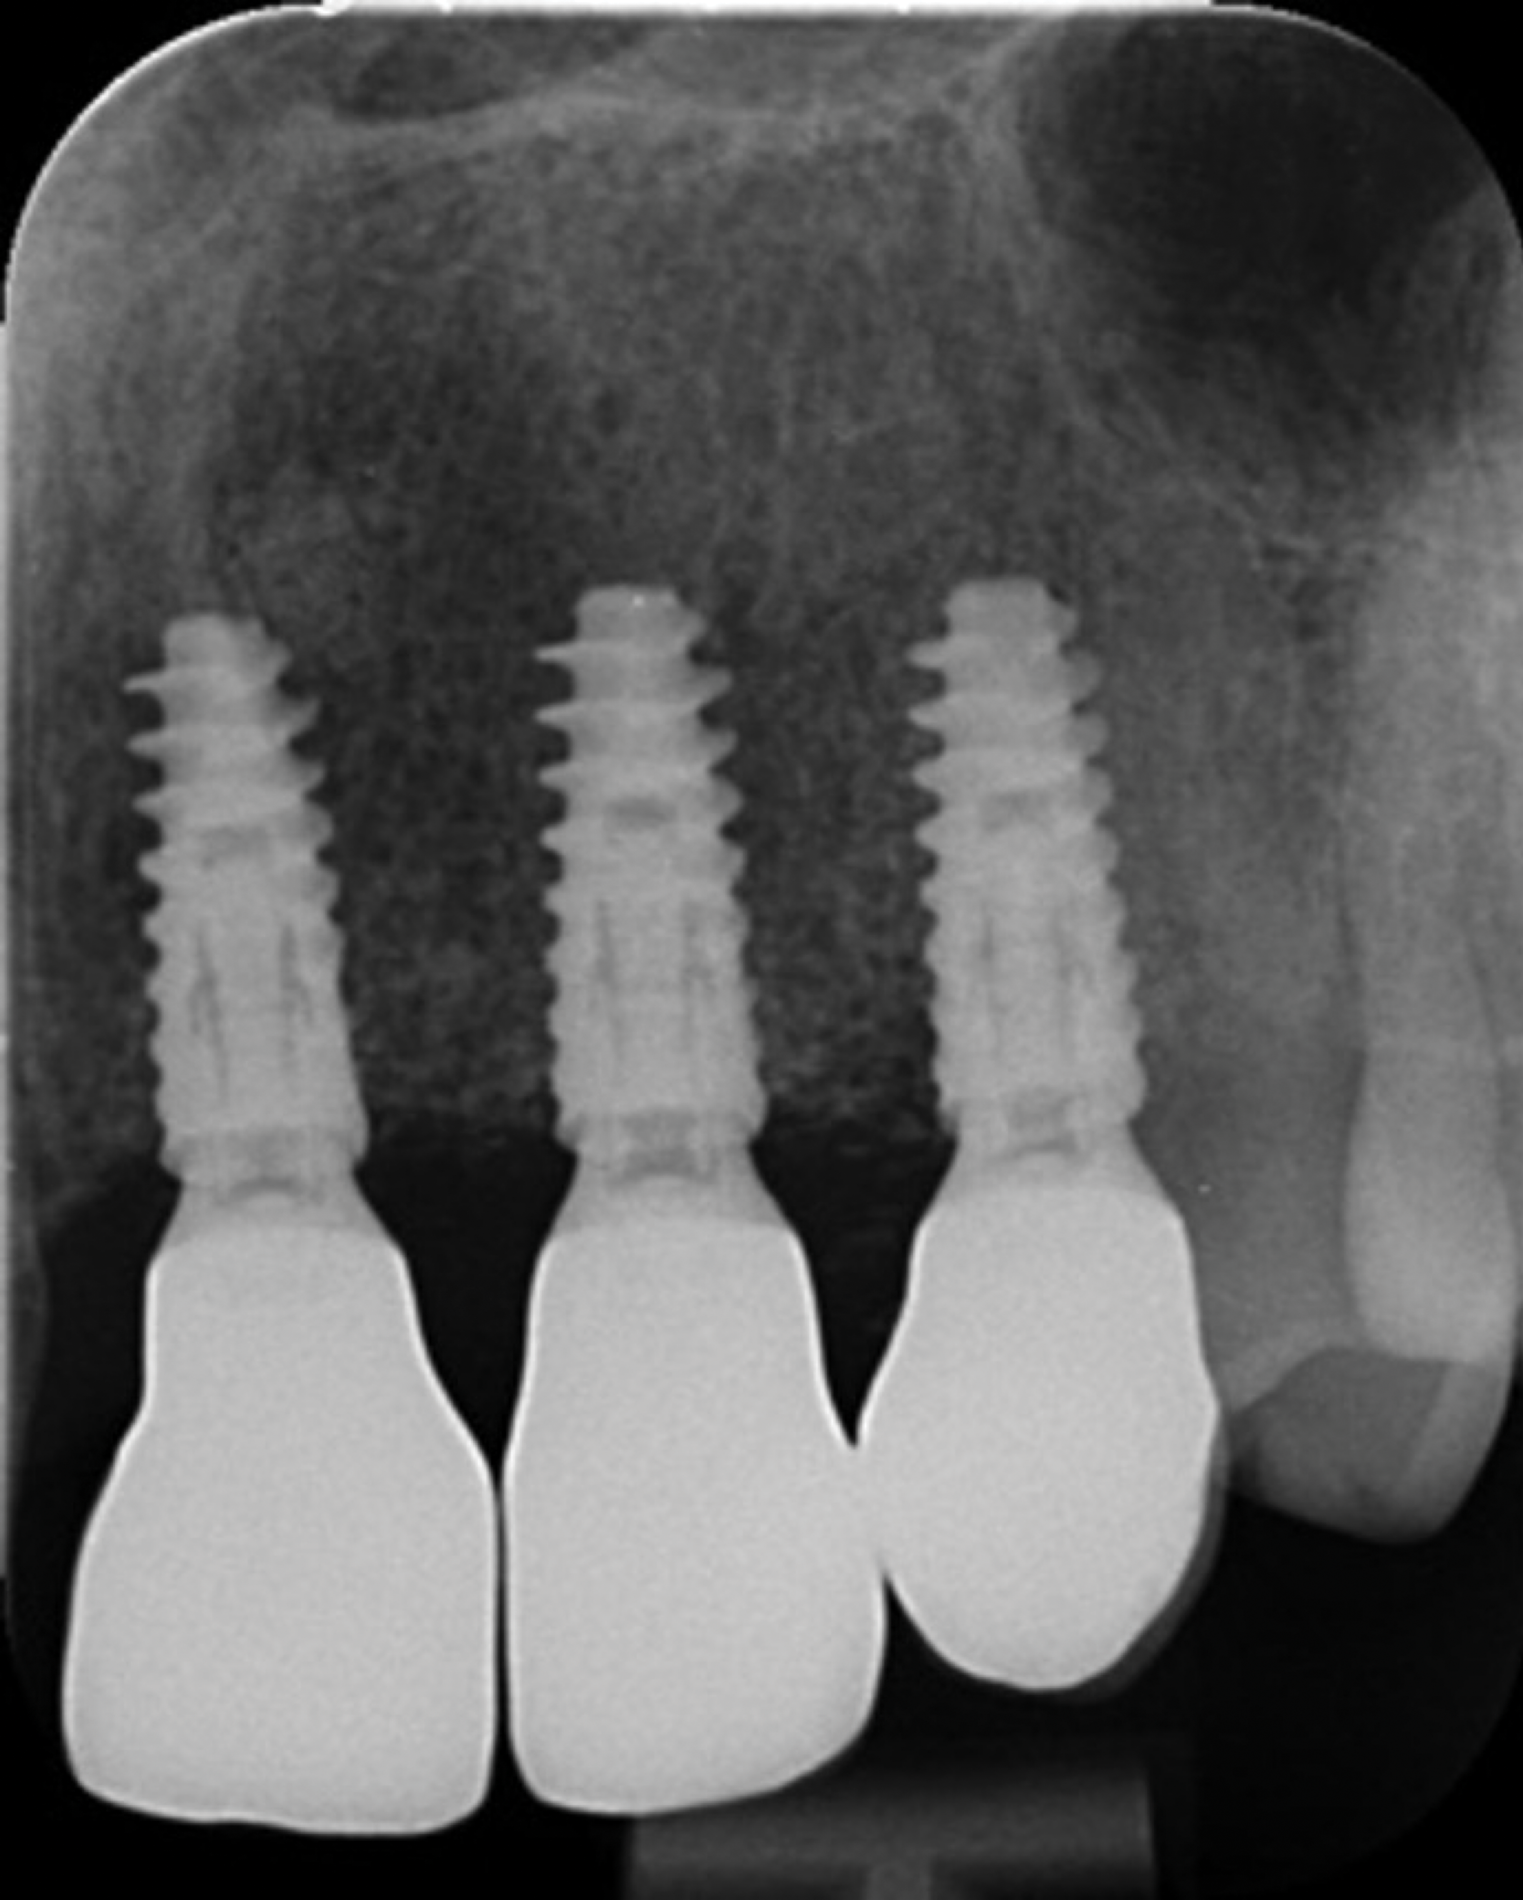

Fig 17. Final radiographic outcome at 12 months post–iCTG augmentation.

Figure 17

After 9 months, the site was reopened and the d-PTFE membrane and titanium pins were retrieved (Figure 9). The regenerated bone volume allowed for the placement of three dental implants (parallel, conical connection) in prosthetically driven positions using a surgical guide (Figure 10).

After 3 months of healing, the second-stage procedure was performed to uncover the dental implants. Then, after 6 months of soft-tissue conditioning with temporary crowns, the case was completed with permanent, implant-supported restorations (Figure 16 and Figure 17).